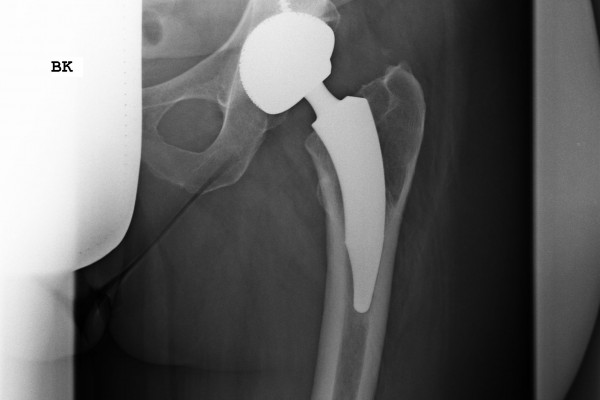

Aufbau eines künstlichen Hüftgelenkes

Das künstliche Hüftgelenk besteht aus vier Komponenten. Im Becken erfolgt die Implantation einer Pfannenkomponente, meist zementfrei, als Pressfit- oder Schraubimplantat. In dieser Titanpfanne wird ein sogenanntes Inlay aus hochverdichtetem Kunststoff verklemmt.

Im Bereich des Oberschenkels wird eine Schaftkomponente zementfrei (aus Titan) oder zementiert (aus einer Kobalt/Chrom Legierung) implantiert. Am oberen Ende befindet sich ein sogenannter Steckkonus auf den der künstliche Hüftkopf (Metall/Keramik/Oxinium) aufgebracht wird. Eine Komponente wird dann zementiert, wenn eine erheblich geminderte Knochendichte oder Osteoporose vorliegt.